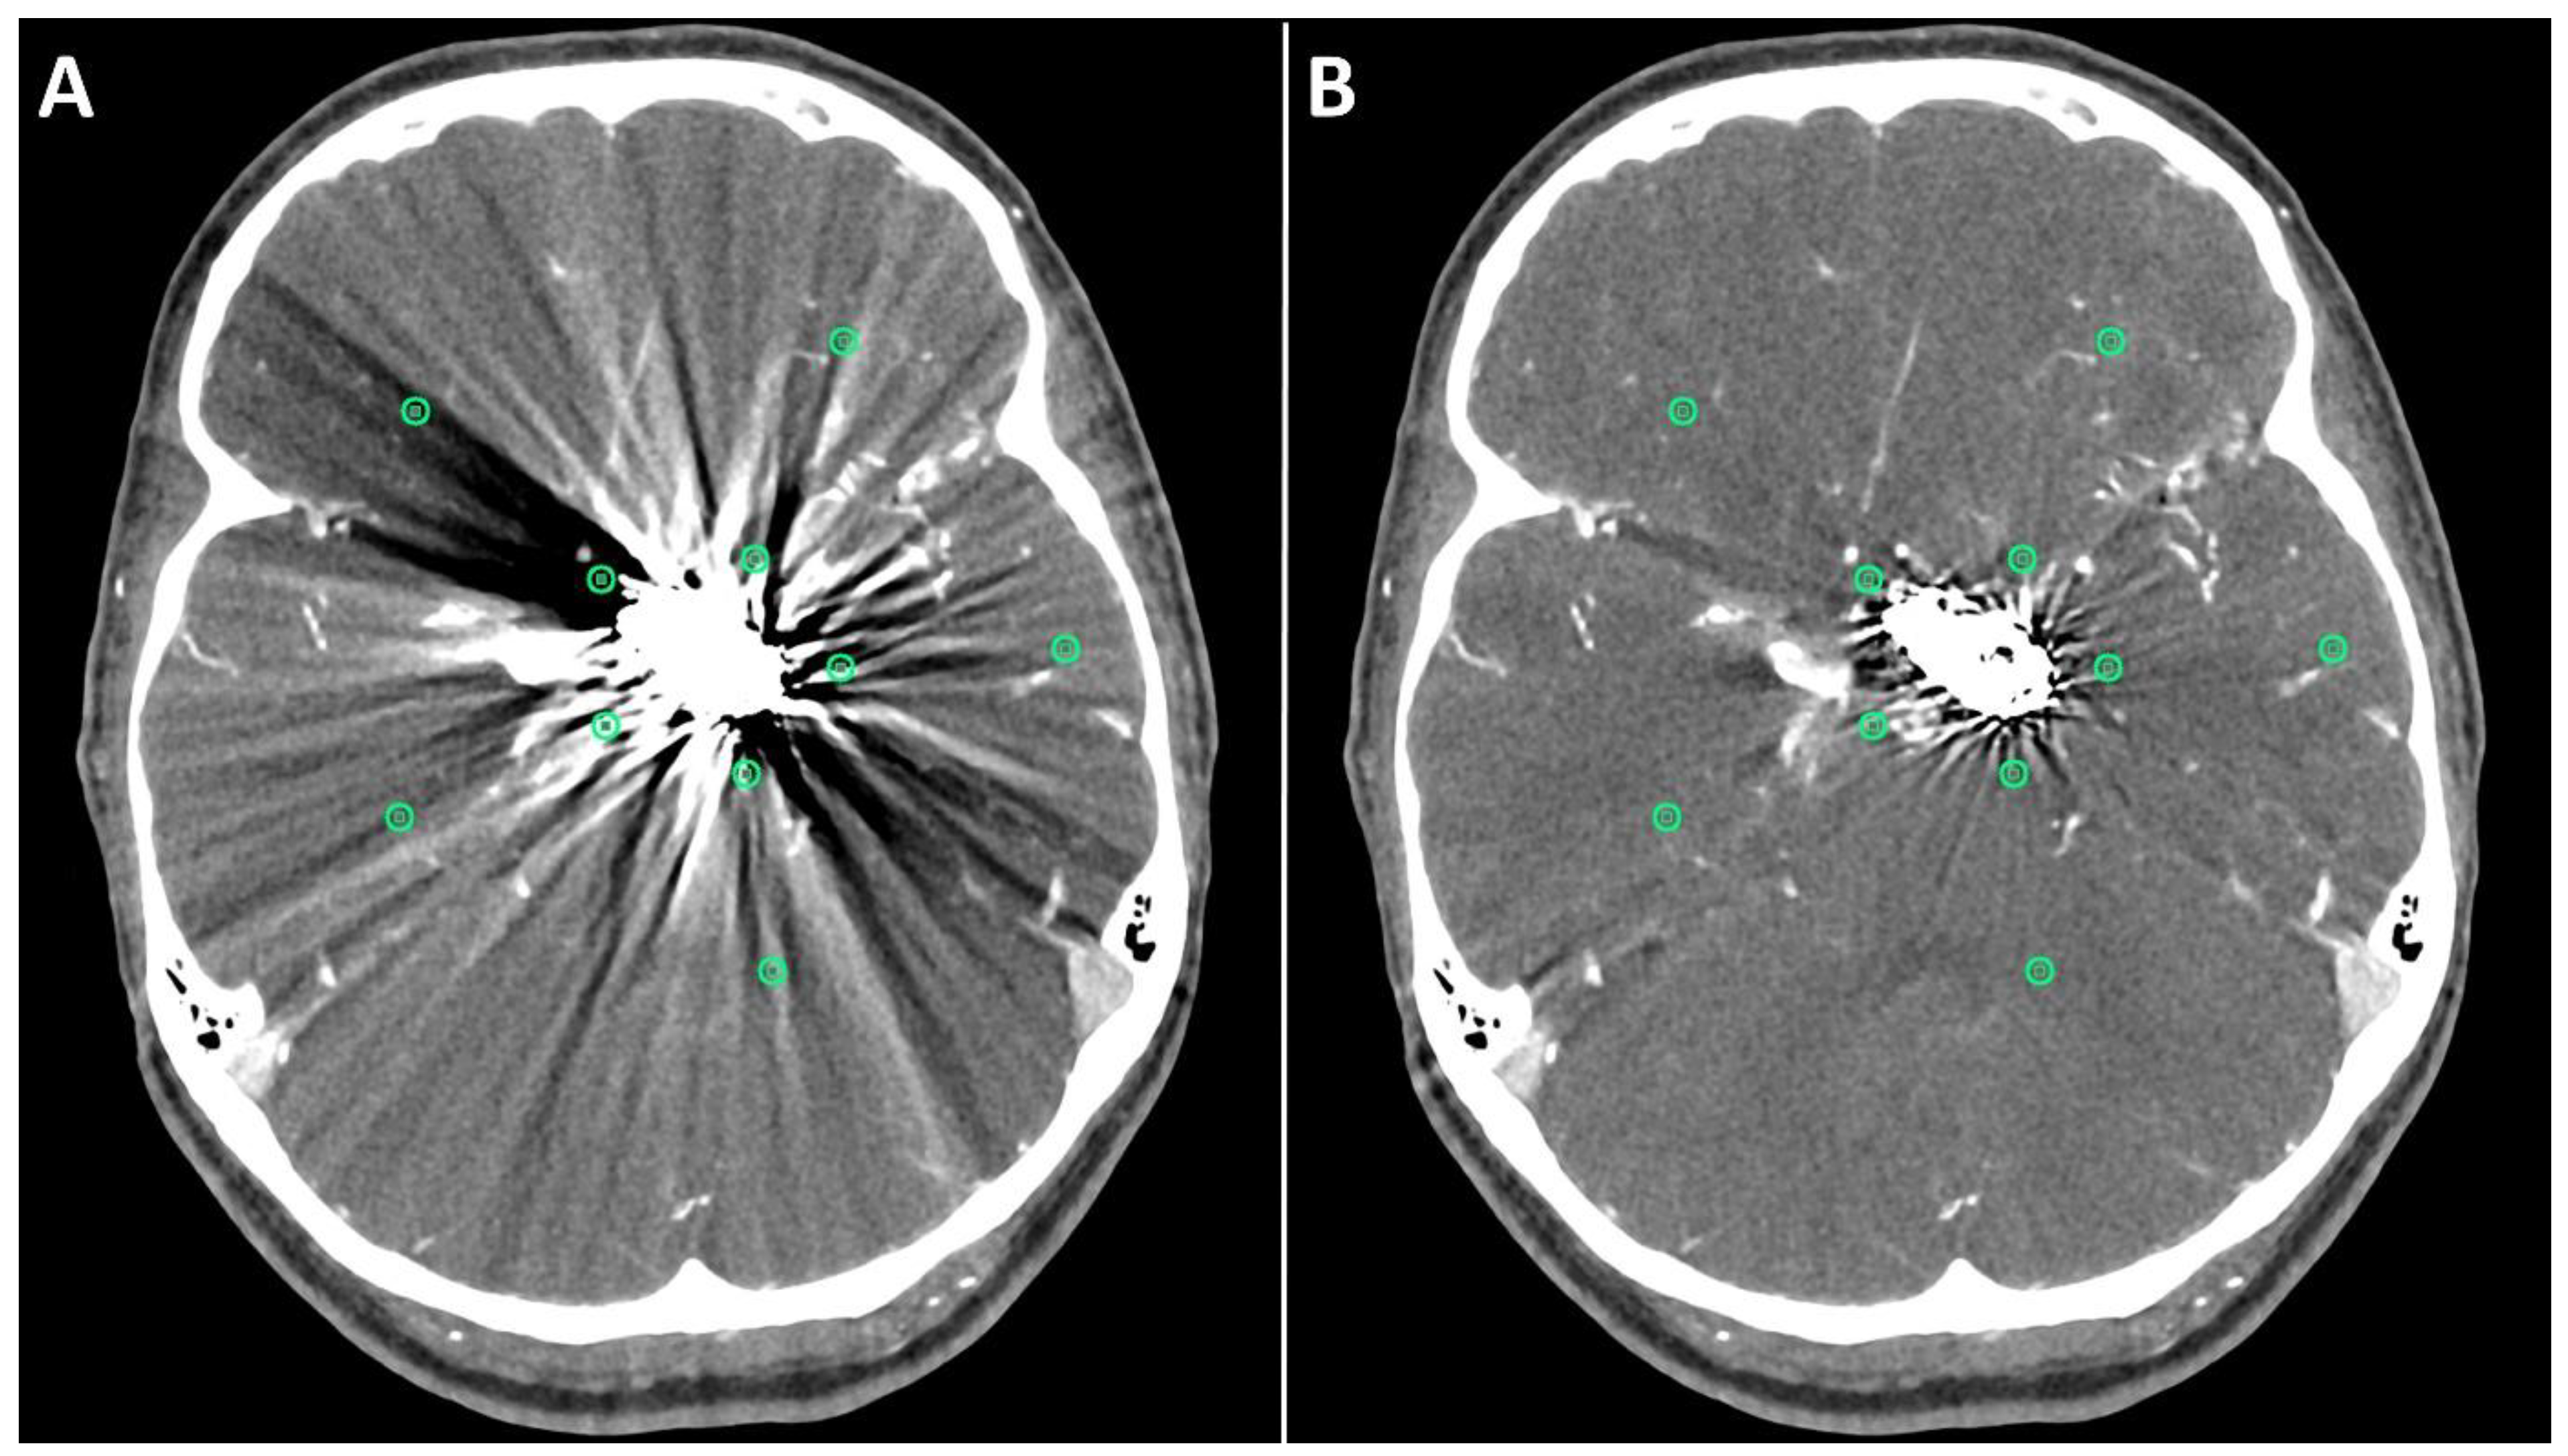

The first method comprised drawing five circular regions of interest (ROIs) with a radius of approximately (10 mm each) in both standard and SEMAR CTA images around the coil/clip mass in close vicinity to the foreign body and five other ROIs more distally from the foreign body in a similar manner to previous reports [8,9,13], while focusing on the artifacts and avoiding the metallic mass, air, and bones (Figure 1). The ROI settings were constant between standard and SEMAR images. The mean density and standard deviation (SD) of each five of the five ROIs were measured in HU (Hounsfield–Units). The average image noise within the ROIs was set as the standard deviation and was considered as an index for the metal artifacts.

Figure 1.

Positioning of ROIs (Region of Interest) for quantitative image analyses on standard (A) and SEMAR (B) CT-angiography images in axial plane (0.25 mm slice thickness) in direct proximity and more distally to the metal implant. In this case, follow up CT-angiography of a 56-year-old female who underwent coil-embolization of a left sided posterior communicating artery aneurysm.